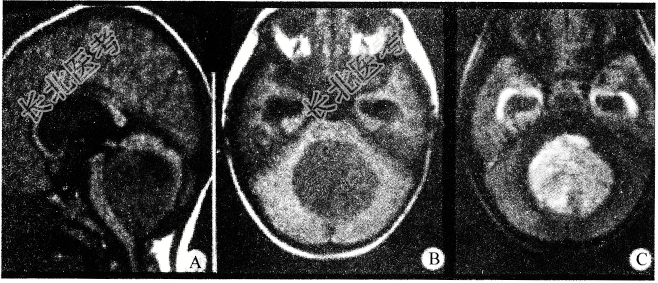

- 单项选择题关于髓母细胞瘤(如图所示)哪项是对的

D、来源于胚胎残余组织